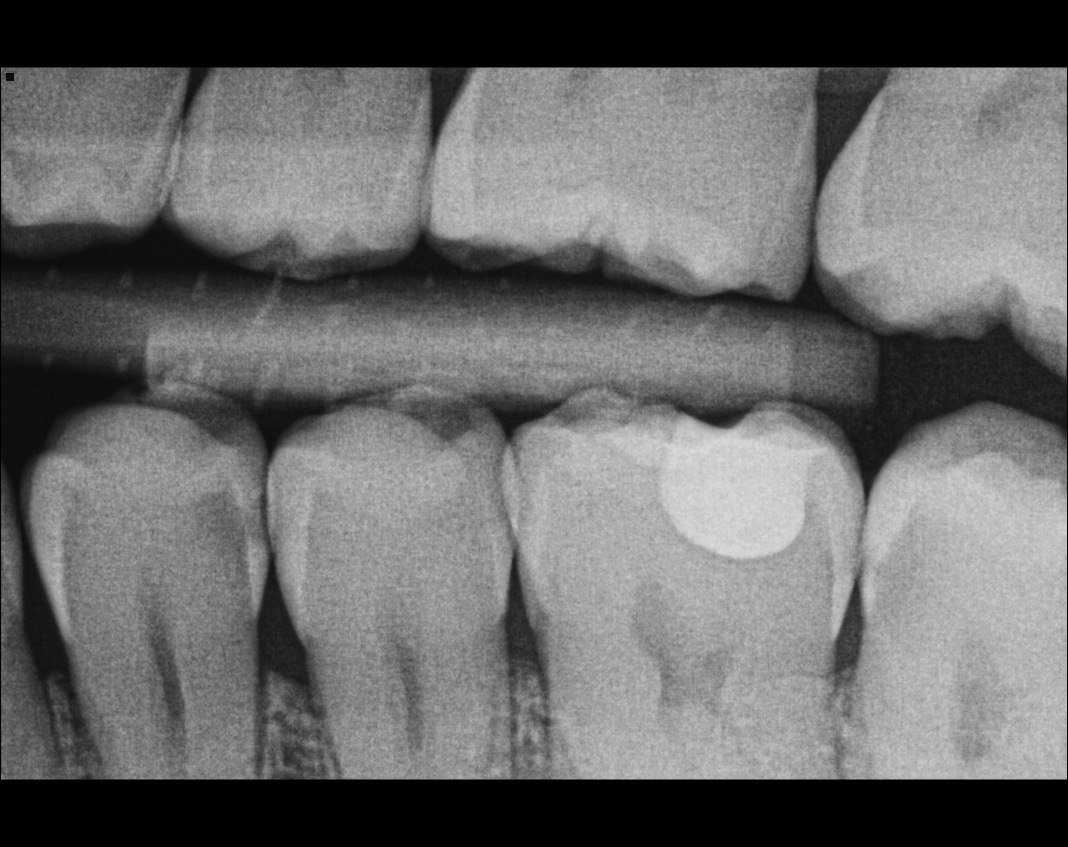

Question 7: What are the options associated with the distal surface of the tooth # 2.1 and mesial surface of the tooth # 2.2 respectively?

Question 8: What is the condition associated with the occlusal surface of the tooth # 1.6?